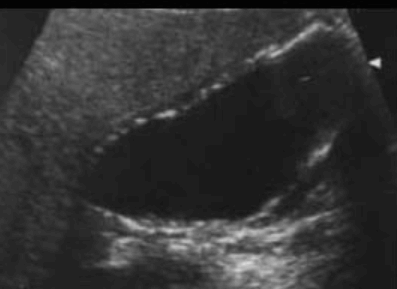

US finding

- 담낭벽 석회화에 의한 소견으로 후방음향음영을 동반한 곡선모양의 고에코를 나타내는 것

- 전벽과 후벽 모두 고에코를 나타내는 것

- 음향음영을 동반하는 불규칙한 고에코가 군집형태를 이루는 것 (암의 가능성이 높다)

- 환자 체위에 따른 변화가 보이지 않는다

- 담낭 내강을 관찰하기 어렵다